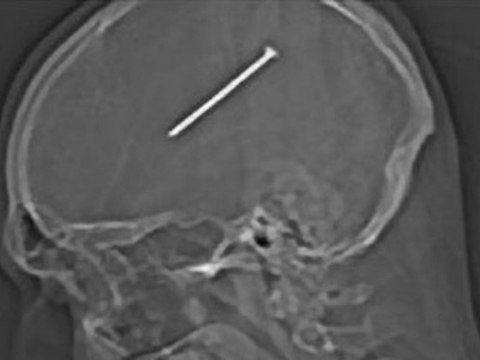

Il frôle la mort à cause d'un harpon

frôle, mort, cause, harpon